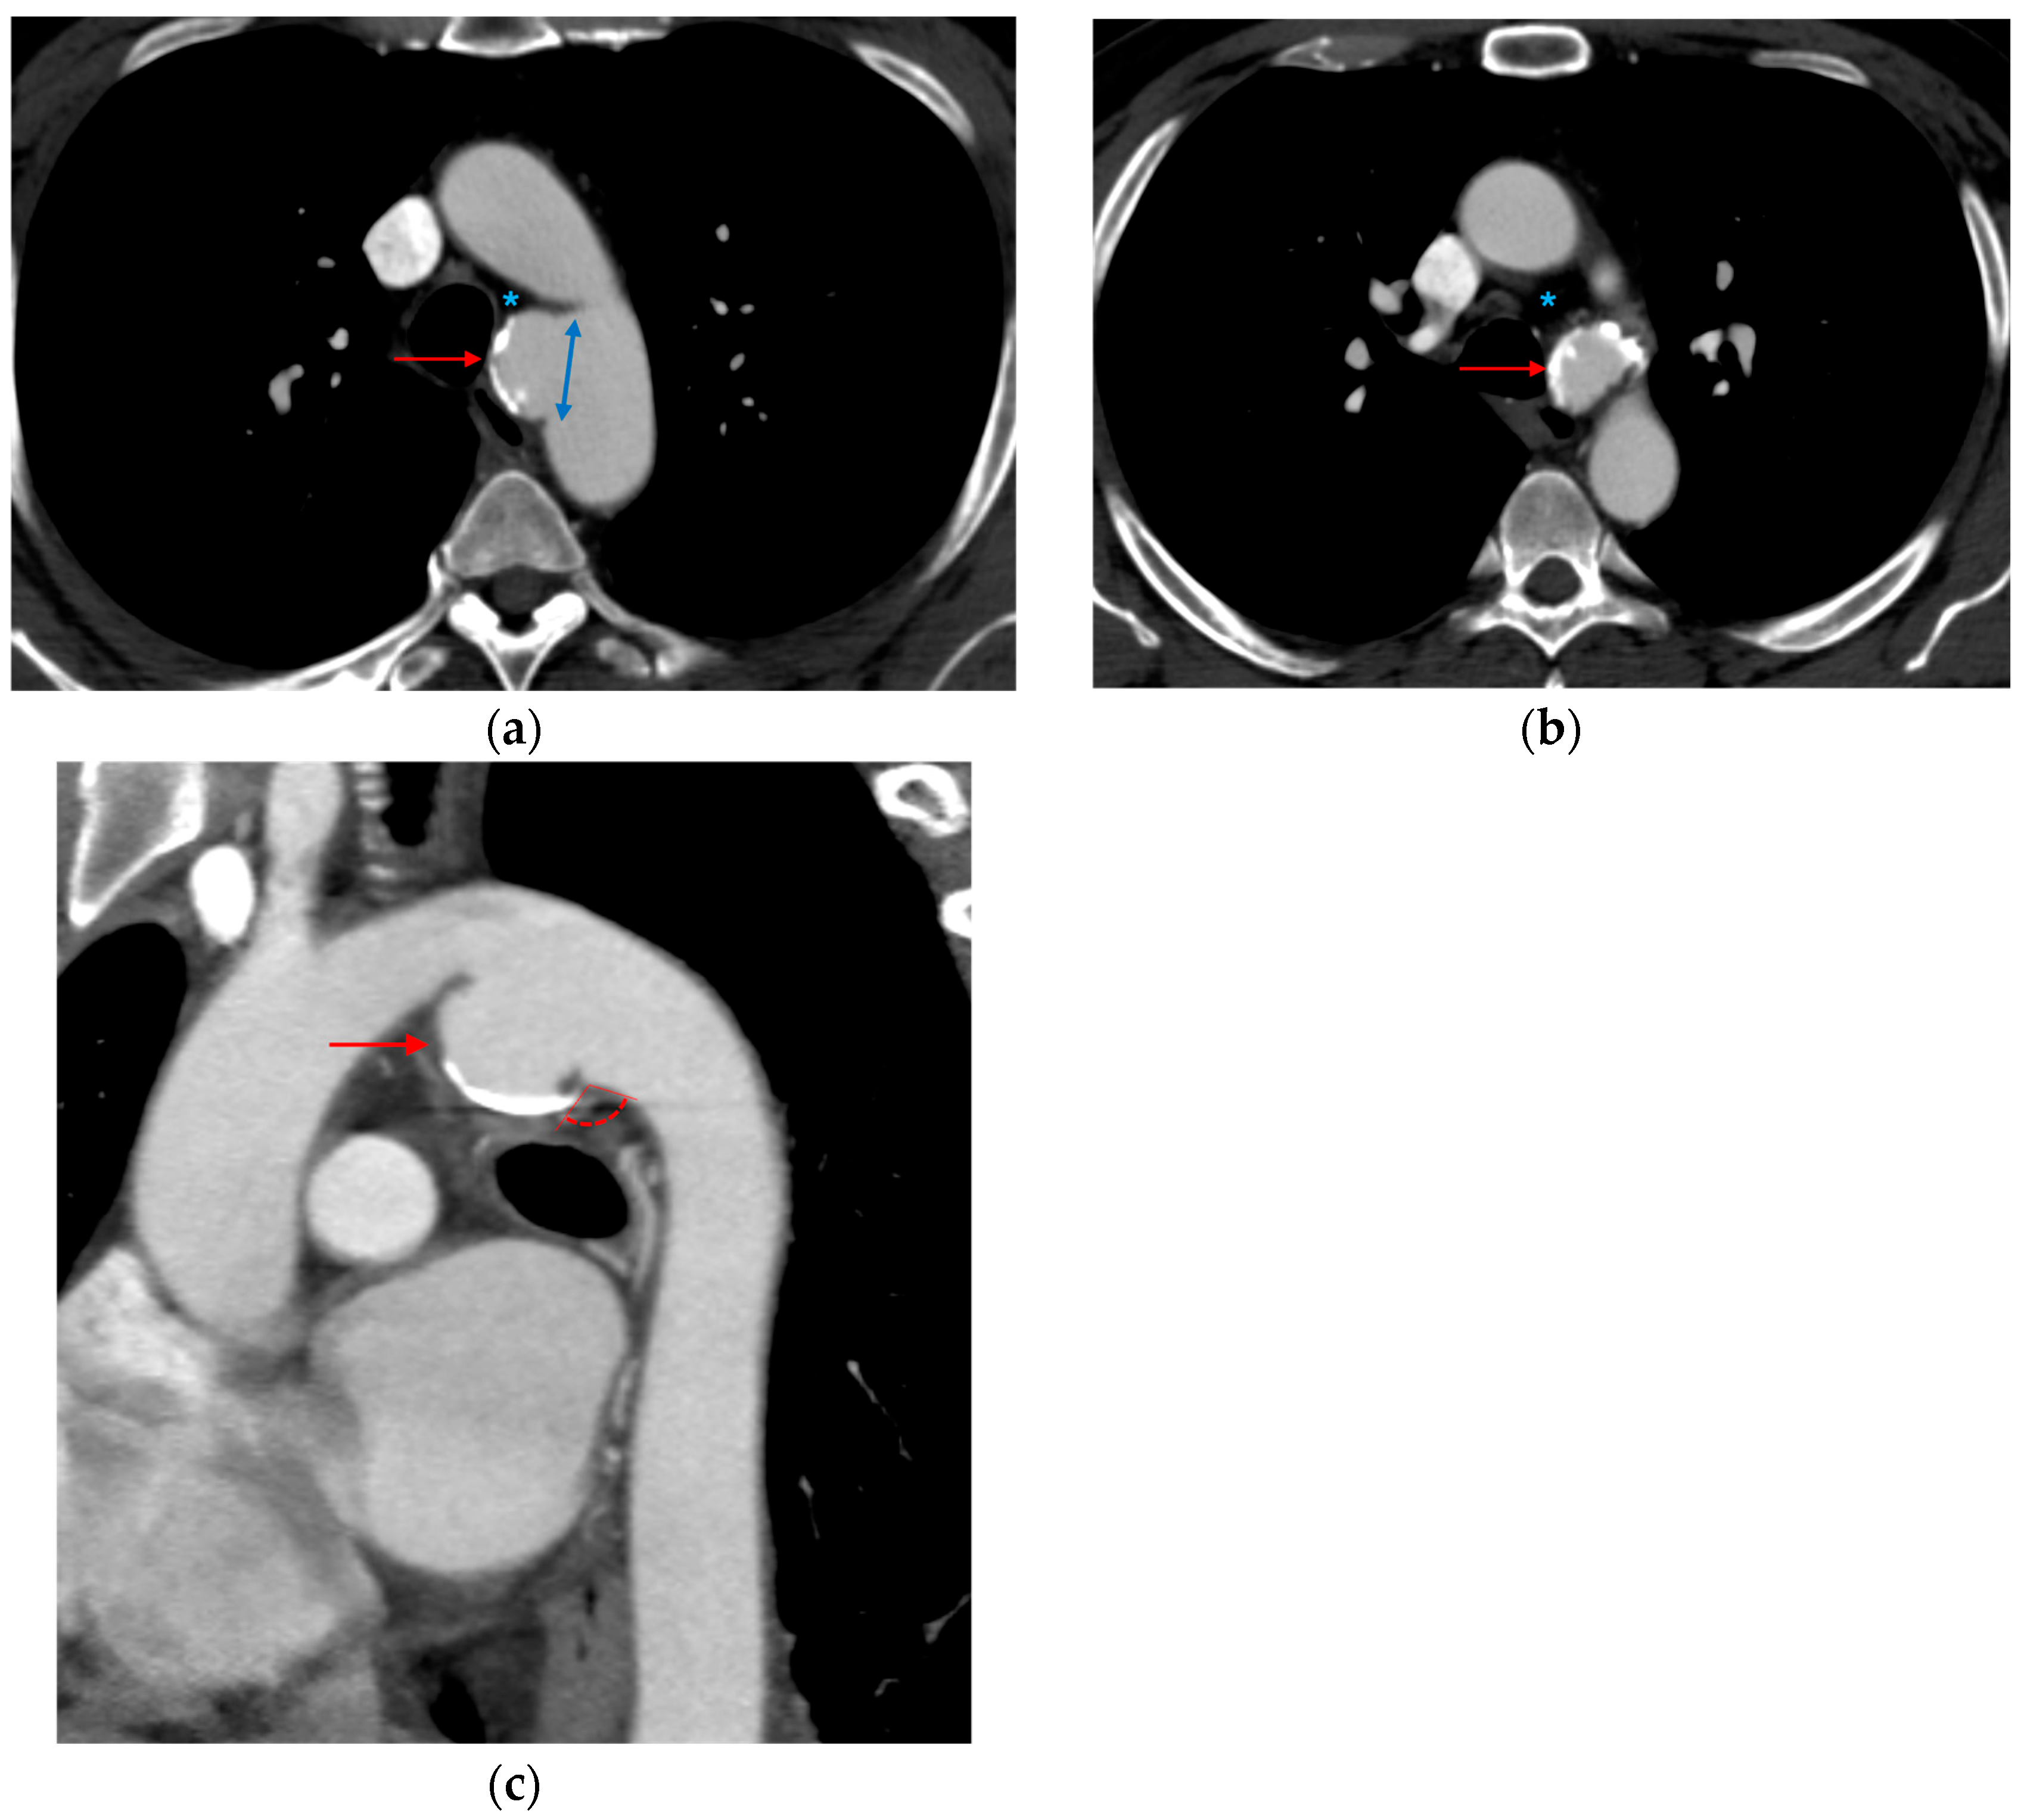

3.1.5. CT Angiography Artifacts

3.1.6. ECG-Gated CT Angiography

6.1.2. Role of Imaging in Preoperative Endovascular Planning